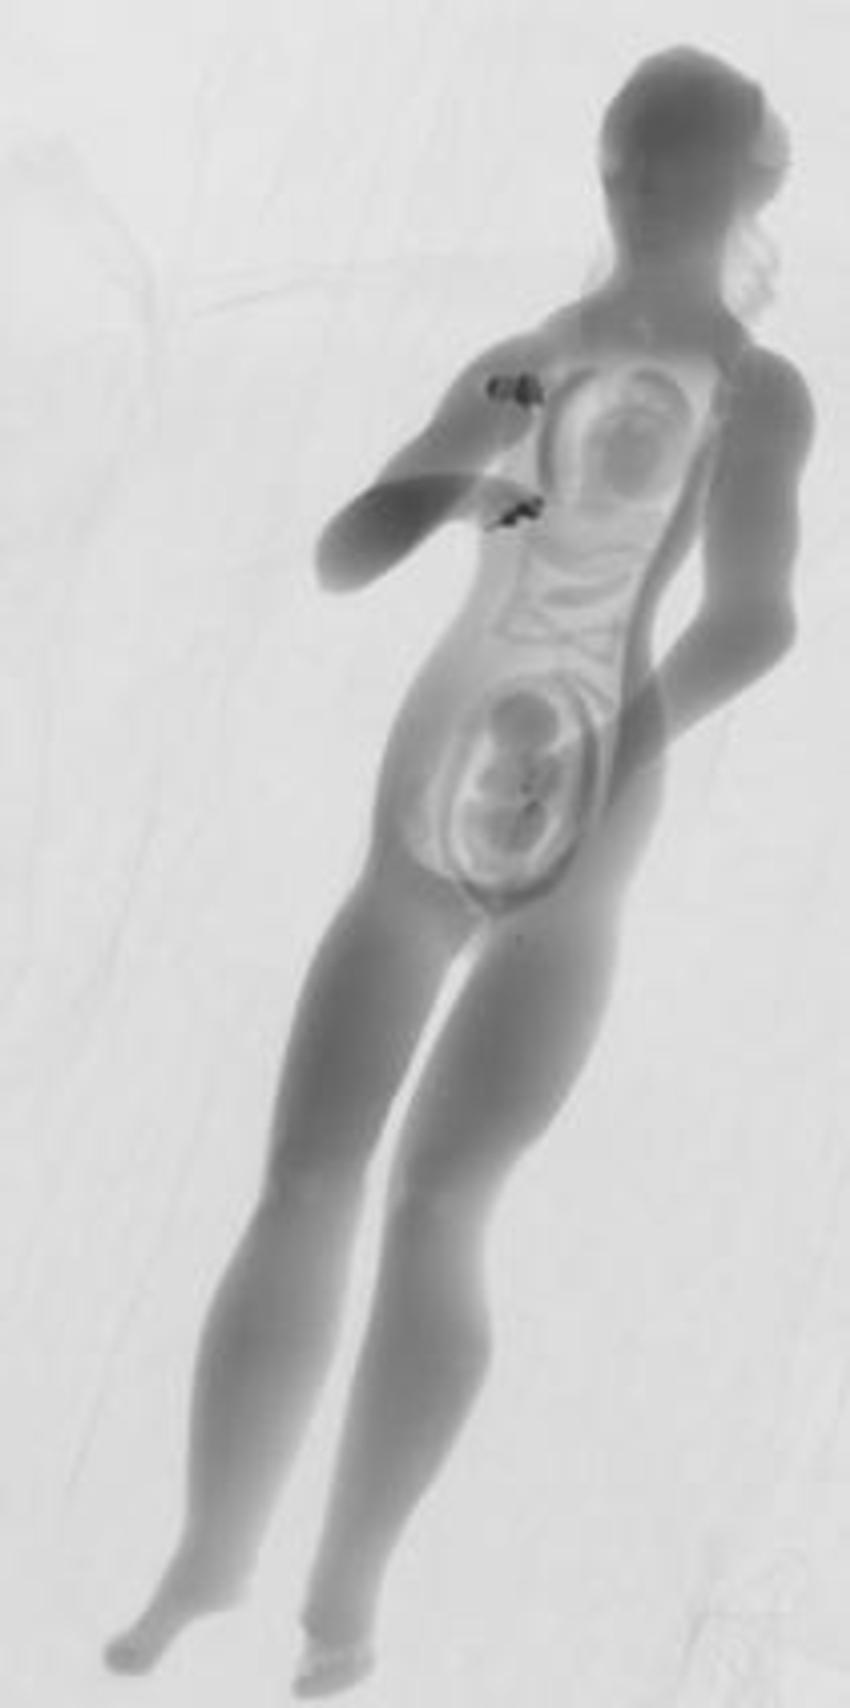

Figure 2. An Ivory manikin after removal of the abdominal and chest wall, ribs, and part of the uterus. Internal organs such as the lungs, intestines, as well as a fetus inside the uterus are visible.

High-res (TIF) version

Figure 3. Micro-CT initial scan data. The internal organs and fetus inside the uterus are visible, similar to a photograph.